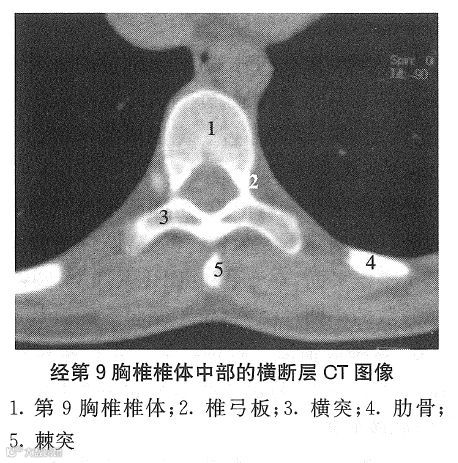

三、胸段横断层解剖

1、椎体 自上而下逐渐增大,中部椎体的横断面呈心形,前凸后凹,矢径略大于横径。上、下部椎体的形态分别向颈、腰椎过渡。由于脊柱胸曲后凸,在经椎间盘的横断层内可出现椎体断面,上位椎体在前,下位椎体在后。相邻椎体侧面的上、下肋凹及其间的椎间盘与肋头构成肋头关节,但第1、10~12对肋的肋头侧与相应椎体的肋凹构成肋头关节。

2、椎弓 胸椎椎弓根短而窄。棘突呈叠瓦状排列,在同一横断层中可见两个棘突断面,上位棘突居后,下位棘突在前,棘突间有棘间韧带相连。关节突扁薄,关节腔呈横位,在同一横断层中,上关节突位前,下关节突在后。横突粗而长,伸向后外上方,除第11、12胸椎横突外,横突末端前面与同序数肋构成肋横突关节。

3、椎间盘 胸椎间盘的横断面形态和大小基本与相邻椎体一致,髓核位于中央。第2~9对肋头依次连于第1~8胸椎间盘两侧。

4、椎管及其内容 胸椎管近似圆形,横径与矢径大致相等,第4~10胸椎平面最小。硬膜囊呈圆形。脊髓位于硬膜囊中央,呈圆形或椭圆形;胸髓最细部的矢、横径分别为6.5mm和7.8mm;腰骶膨大主要在第11、12胸椎平面,其矢、横径分别为8.3mm和10.3mm。蛛网膜下隙的矢径约12~13mm,但第9~12胸椎平面的略大。硬膜外隙窄,脂肪少。

5、椎间孔(管)和神经根 胸椎间孔(管)呈横向,前壁为椎体和椎间盘,后壁为上关节突,上、下壁分别为相邻椎骨的椎弓根。胸神经根通过相应椎间孔上部,椎间孔下部容有血管和脂肪,其外侧毗邻肋颈。